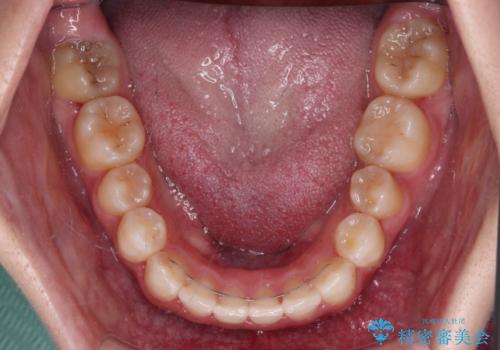

前から5番目の乳歯は、後続永久歯である小臼歯と比べて幅径が大きいため、移動に時間がかかりましたが、きれいに仕上げることができました。